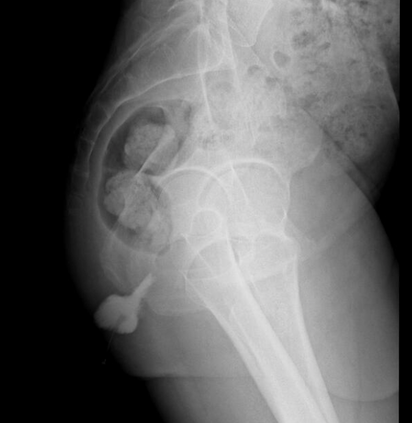

In this study, we aim to initiate the development of Radiology Foundation Model, termed as RadFM.We consider the construction of foundational models from the perspectives of data, model design, and evaluation thoroughly. Our contribution can be concluded as follows: (i), we construct a large-scale Medical Multi-modal Dataset, MedMD, consisting of 16M 2D and 3D medical scans. To the best of our knowledge, this is the first multi-modal dataset containing 3D medical scans. (ii), We propose an architecture that enables visually conditioned generative pre-training, allowing for the integration of text input interleaved with 2D or 3D medical scans to generate response for diverse radiologic tasks. The model was initially pre-trained on MedMD and subsequently domain-specific fine-tuned on RadMD, a radiologic cleaned version of MedMD, containing 3M radiologic visual-language pairs. (iii), we propose a new evaluation benchmark that comprises five tasks, aiming to comprehensively assess the capability of foundation models in handling practical clinical problems. Our experimental results confirm that RadFM significantly outperforms existing multi-modal foundation models. The codes, data, and model checkpoint will all be made publicly available to promote further research and development in the field.